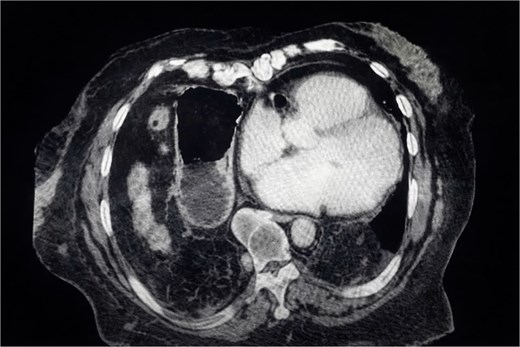

Chest X-ray (Fig. 1) showed elevation of the right hemidiaphragm, diaphragmatic eventration, obliteration of the left subdiaphragmatic recess, and a subdiaphragmatic colonic air-fluid level. Computed tomography (CT) (Fig. 2) confirmed a large right anterolateral diaphragmatic hernia with a craniocaudal extent of ~16 cm and a hernia neck measuring 2 × 5 cm. Measurements were obtained from multiplanar CT reconstructions and reflected the hernia sac size and defect width. A small left-sided fat-containing diaphragmatic hernia (collar 12 mm) and a right uncomplicated inguinal hernia containing distal ileum were also identified.

CT scan showing a large right anterolateral diaphragmatic hernia with a maximal craniocaudal extent.